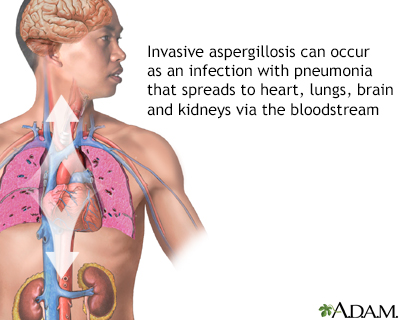

Pulmonary aspergilloma Information Mount Sinai New York

4 key things to know about lung infections caused by fungi discount, Frontiers Pathogenic Fungal Infection in the Lung discount, Fungal Pneumonia Overview Risk Factors Epidemiology of Fungal discount, Pulmonary aspergilloma Information Mount Sinai New York discount, 3 common types of lung fungus Vinmec discount, Fungal Lung Disease Makes World s Deadliest Bacteria Even Worse discount, Fungal infections of the lung in children Pediatric Radiology discount, World s first clinical guidelines for chronic fungal lung infections discount, Pulmonary fungal infection Imaging findings in immunocompetent discount, Frontiers Recent Advances in Fungal Infections From Lung discount, Fungal Pneumonia Overview Risk Factors Epidemiology of Fungal discount, Pulmonary fungal infection Imaging findings in immunocompetent discount, Is it TB or a fungal lung infection New life saving guidelines discount, Fungal pneumonia causes symptoms diagnosis treatment discount, COVID 19 associated pulmonary aspergillosis caused by aspergillus discount, Fungi are present in your lungs Faculty of Medicine UiB discount, Aspergillus Pneumonia Appears to Be Most Common Fungal Infection discount, CT image of lung with pulmonary Candida infection. There are many discount, A Schizophyllum commune fungus ball in a lung cancer cavity a discount, Fatal Fungal Lung infection affects TB recovered patients due to discount, Respiratory Mycoses Microbiology discount, Pulmonary fungal infection Imaging findings in immunocompetent discount, What is Aspergillosis Fungal Infections Symptoms Video discount, Blastomycosis Wikipedia discount, How nanoparticle drug inhalation helps fungal lung infections discount, Aspergillosis Types of Fungal Diseases Fungal Diseases CDC discount, Fungal pneumonia Wikipedia discount, Frontiers Candida Colonization in the Respiratory Tract What Is discount, How to fight fungal infection the path of yeast resistance discount, Pulmonary aspergilloma Information Mount Sinai New York discount, Fungal Infection Not Just Toenails Blueberry Therapeutics discount, Lung disease fungus grows here discount, Frontiers Case Report Invasive Fungal Infection and Daratumumab discount, A case report of fungal infection associated acute fibrinous and discount, Mice found able to ward off fungal lung infections by causing discount.

4 key things to know about lung infections caused by fungi discount, Frontiers Pathogenic Fungal Infection in the Lung discount, Fungal Pneumonia Overview Risk Factors Epidemiology of Fungal discount, Pulmonary aspergilloma Information Mount Sinai New York discount, 3 common types of lung fungus Vinmec discount, Fungal Lung Disease Makes World s Deadliest Bacteria Even Worse discount, Fungal infections of the lung in children Pediatric Radiology discount, World s first clinical guidelines for chronic fungal lung infections discount, Pulmonary fungal infection Imaging findings in immunocompetent discount, Frontiers Recent Advances in Fungal Infections From Lung discount, Fungal Pneumonia Overview Risk Factors Epidemiology of Fungal discount, Pulmonary fungal infection Imaging findings in immunocompetent discount, Is it TB or a fungal lung infection New life saving guidelines discount, Fungal pneumonia causes symptoms diagnosis treatment discount, COVID 19 associated pulmonary aspergillosis caused by aspergillus discount, Fungi are present in your lungs Faculty of Medicine UiB discount, Aspergillus Pneumonia Appears to Be Most Common Fungal Infection discount, CT image of lung with pulmonary Candida infection. There are many discount, A Schizophyllum commune fungus ball in a lung cancer cavity a discount, Fatal Fungal Lung infection affects TB recovered patients due to discount, Respiratory Mycoses Microbiology discount, Pulmonary fungal infection Imaging findings in immunocompetent discount, What is Aspergillosis Fungal Infections Symptoms Video discount, Blastomycosis Wikipedia discount, How nanoparticle drug inhalation helps fungal lung infections discount, Aspergillosis Types of Fungal Diseases Fungal Diseases CDC discount, Fungal pneumonia Wikipedia discount, Frontiers Candida Colonization in the Respiratory Tract What Is discount, How to fight fungal infection the path of yeast resistance discount, Pulmonary aspergilloma Information Mount Sinai New York discount, Fungal Infection Not Just Toenails Blueberry Therapeutics discount, Lung disease fungus grows here discount, Frontiers Case Report Invasive Fungal Infection and Daratumumab discount, A case report of fungal infection associated acute fibrinous and discount, Mice found able to ward off fungal lung infections by causing discount.